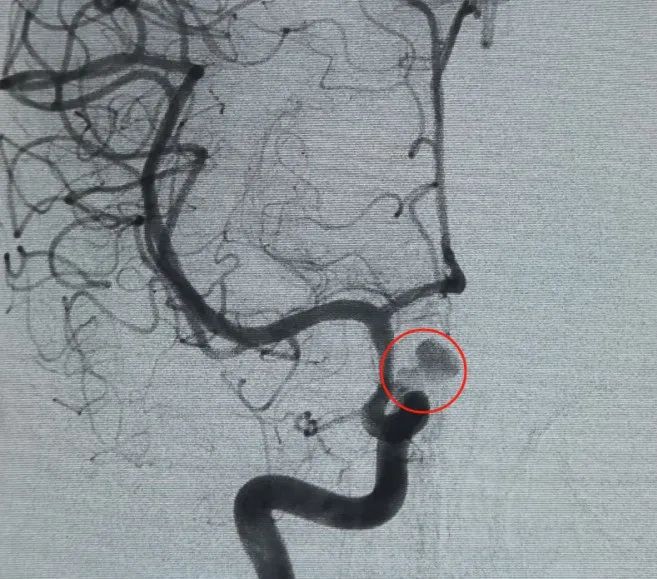

血管アクセスは、大腿動脈穿刺とPerdenserを介して確立されました®6mm × 20 cmの3Dコイルが最初に配備されてバスケットを形成し、安定した壁の配置を実現し、安全な静脈内サポートを提供しました。 これに続いてPerdenserが挿入されました®6mm × 15 cmの3Dコイルで、葉状の娘嚢内の血流を妨害します。

パーフィラー®3mm × 6 cmの拡大可能なコイルおよびパーフィラー®次いで、3mm × 2 cmの拡張可能なコイルを配置して、首の咬合を完了させた。 その後、ヌバ®フローダイバーター (TJED-D-5.0-16) を投与し、動脈瘤の首全体に展開しました。 前後および横方向の両方のビューでの追跡血管造影により、優れたカバレッジ、良好な壁の配置、および明確な放射線不透明度が確認され、顕著なコントラストの停滞が確認されました。